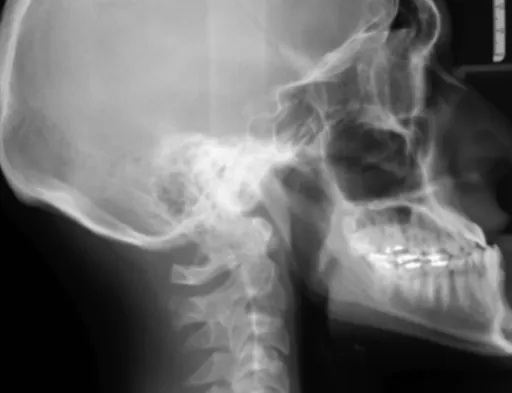

귀 질환의 모든 것: 청각부터 평형 감각까지

우리 귀는 단순히 소리를 듣는 기관을 넘어서, 몸의 균형을 잡는 데에도 아주 중요한 역할을 한답니다. 그래서 귀에 문제가 생기면 소리가 잘 안 들리는 난청은 물론, 어지럼증까지 느낄 수 있어요. 이비인후과에서는 이런 다양한 귀 질환을 세심하게 진단하고 치료하고 있답니다.